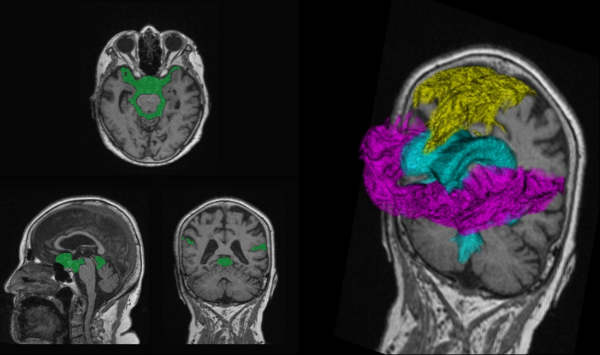

脳脊髄液腔解析

「治療で改善できる認知症」と言われているハキム病(特発性正常圧水頭症:iNPH)は、特徴的な所見であるくも膜下腔の不均衡分布(DESH)が発生することが知られている。「脳脊髄液腔解析」では脳脊髄液腔のDESHに関係する各領域を自動でセグメンテーションし、領域ごとの体積や領域間の体積比を算出することができる。これによって、ハキム病の診断に重要な画像所見であるDESHの判定に寄与することが期待される。

黄色:高位円蓋部・正中のくも膜下腔、水色:脳室、赤紫色:シルビウス裂・脳底槽